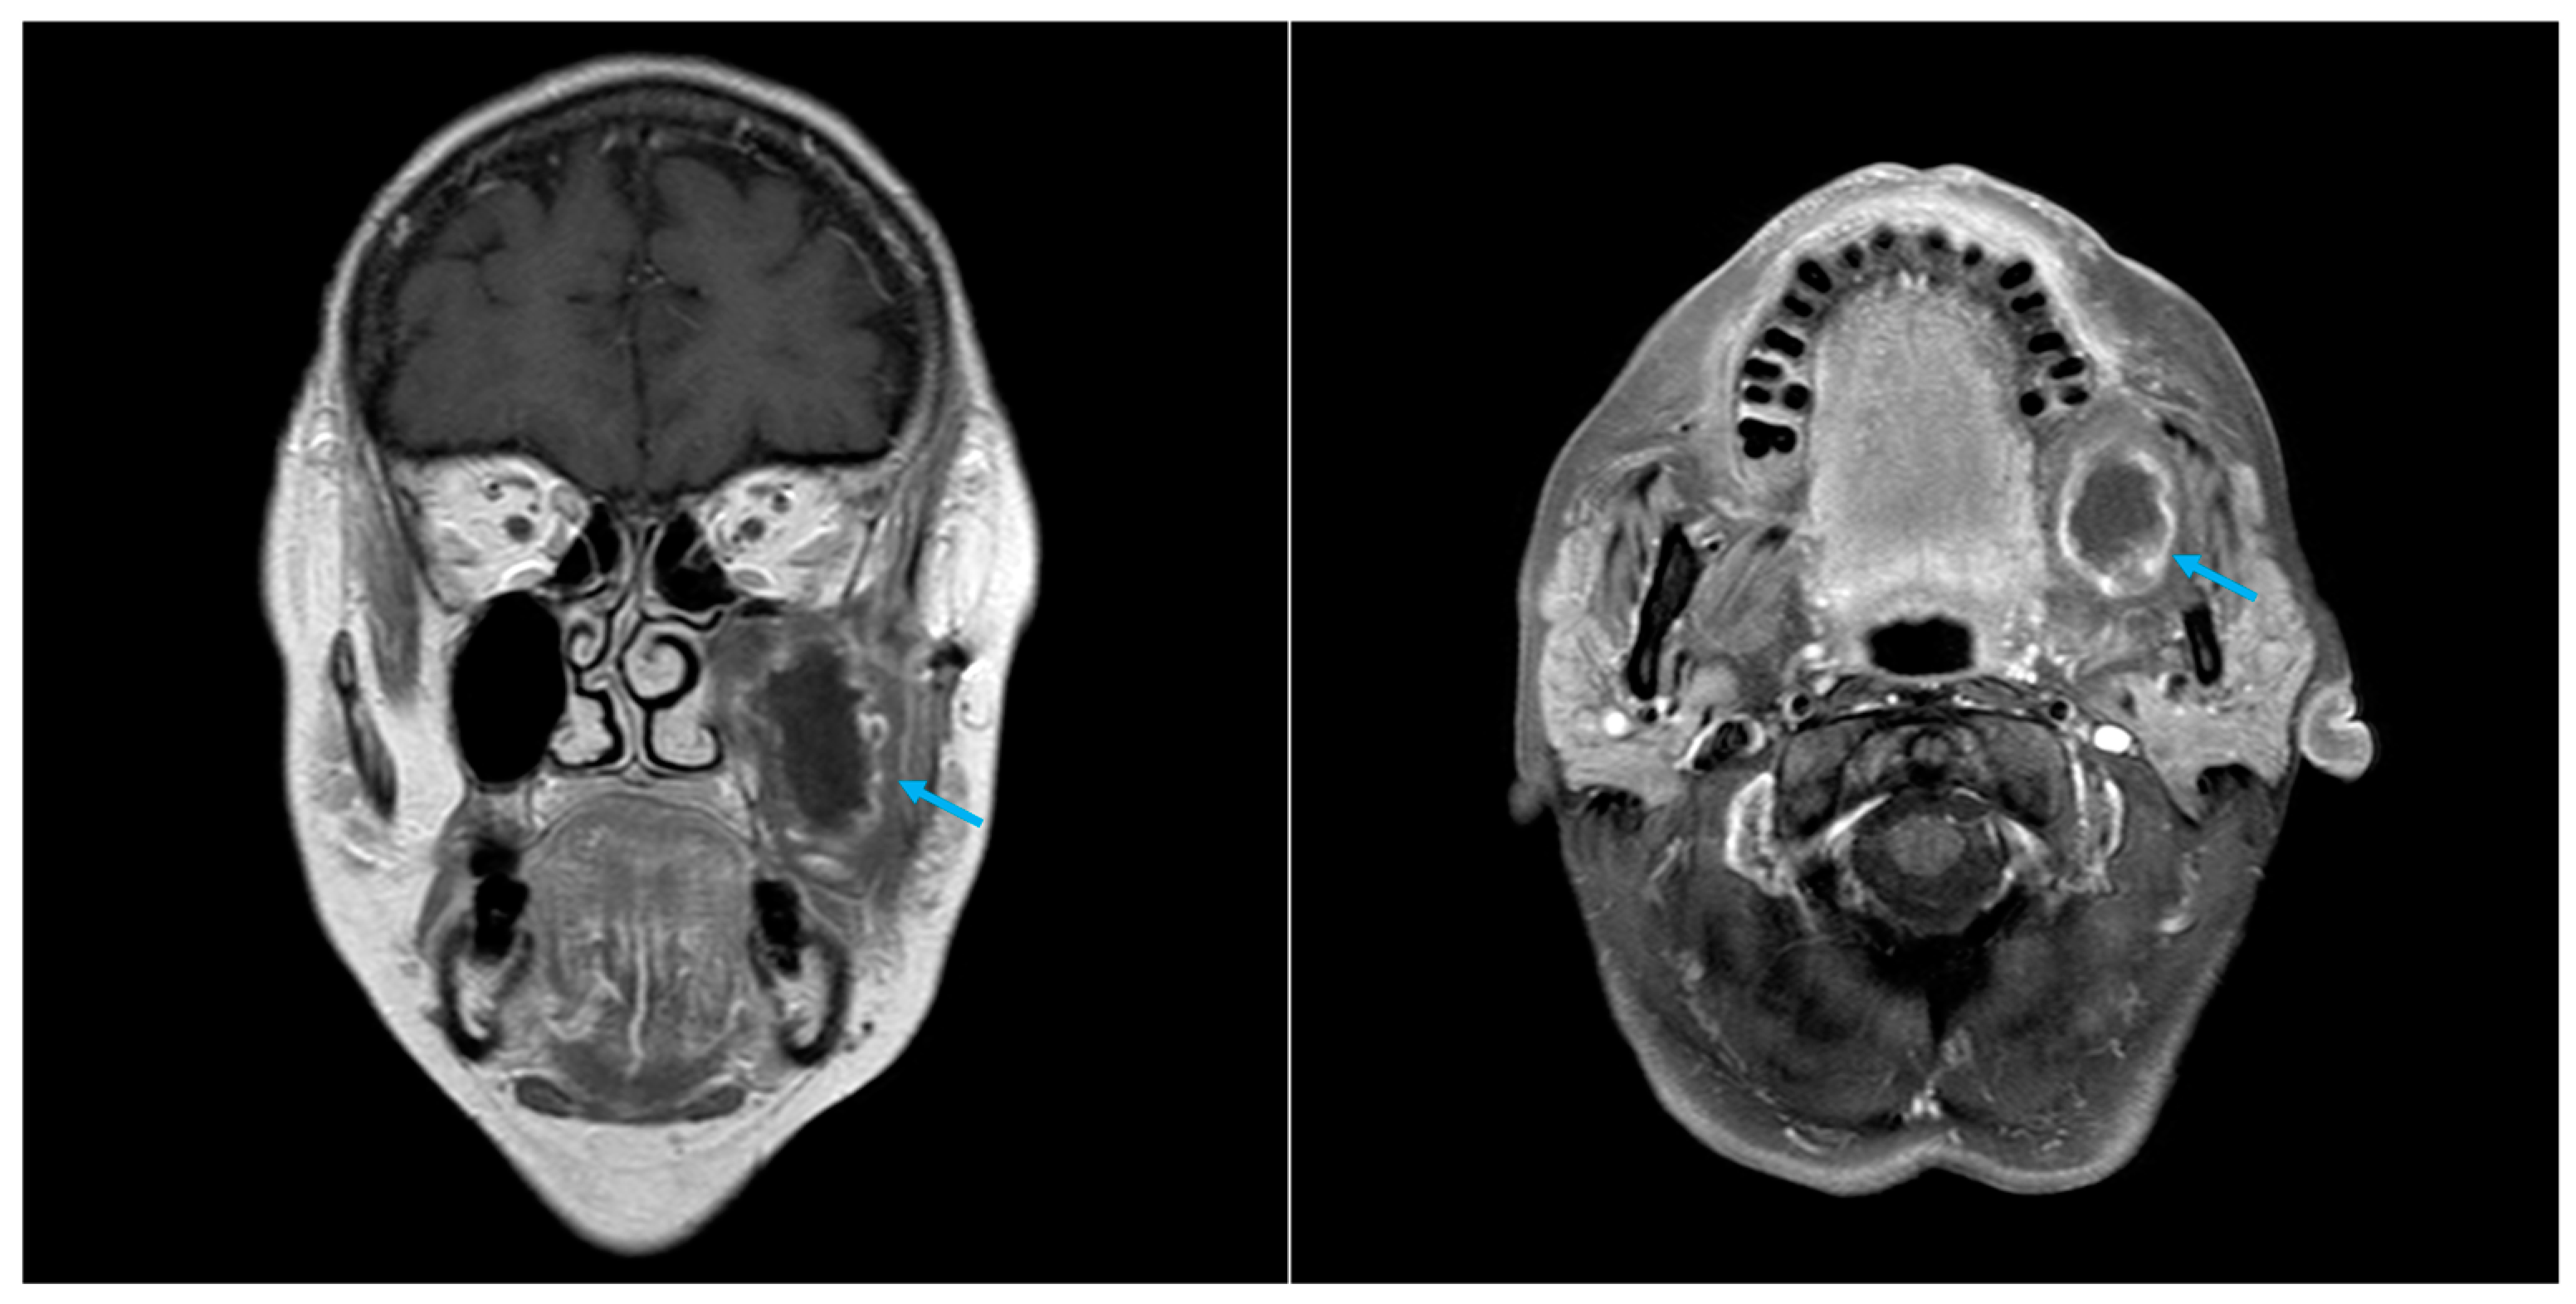

| Presented case 2 | 2024 | Case report | 1 | 69 | M | Oral cavity | Tabotamp | SCC | Hemimandibulectomy, omolateral neck dissection and free flap reconstruction | CT + US | 30 d | CT + FNAC | C |

| Case 2 | Residual tissue with a peripheral solid portion with contrast enhancement and a central hypodense area likely representing fluid, with concurrent air bubbles | Peripheral solid portion, with slight contrast enhancement (T1), and a central colliquated portion | H: Fibrous tissue fragments w histiocytic–macrophagic nature, mixed with neutrophil granulocytes and calcific-like material | |||